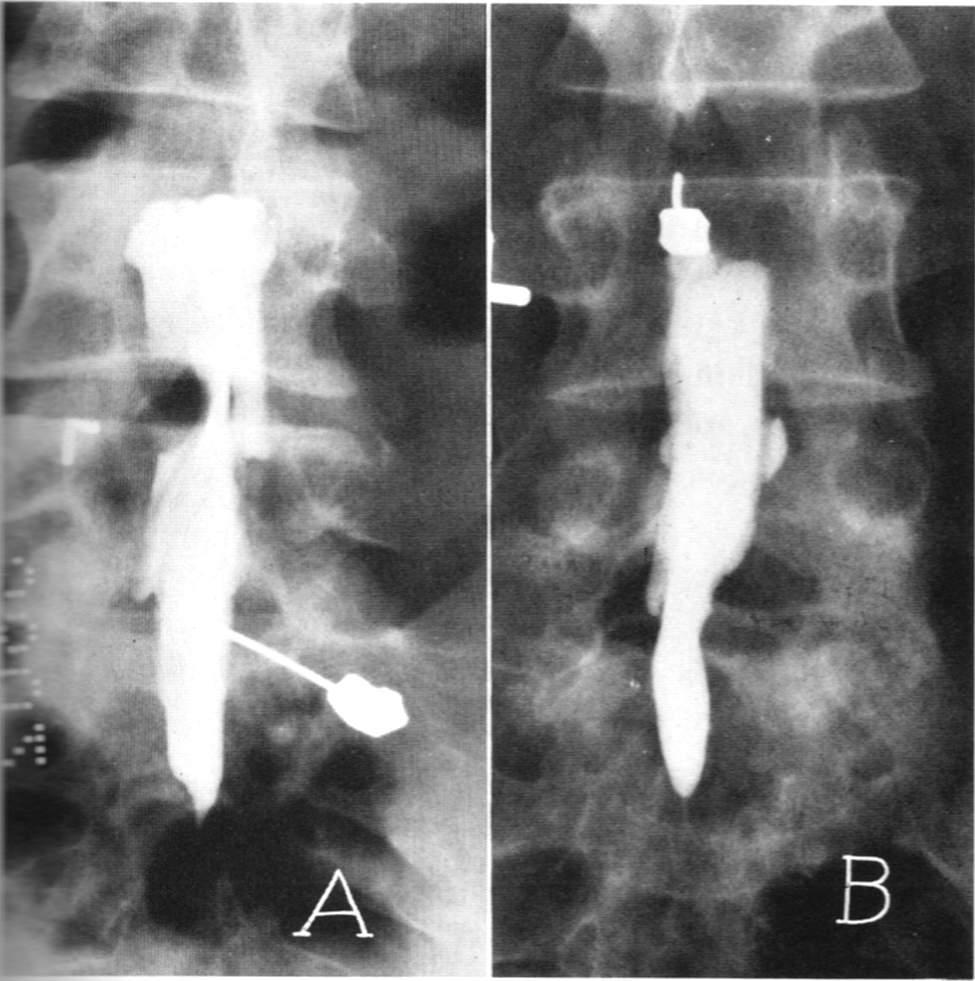

脊髓造影:往脊髓腔里面打造影剂后拍个片子,准确率可以达到80%,但无法良好的显示神经根,同时有创,一般很少用。